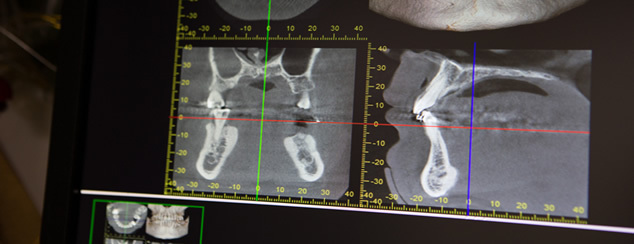

当院では、感染を防ぐための滅菌の徹底、CTスキャンによって骨・血管・神経の状態を立体的に把握した上で、それらを傷つけないようにインプラントを入れる箇所を決定するなどの処置をしています。

本数が多いときなどは、インプラントをシミュレーションしたサージカルステントという模型状のものを入れながらスキャンします。